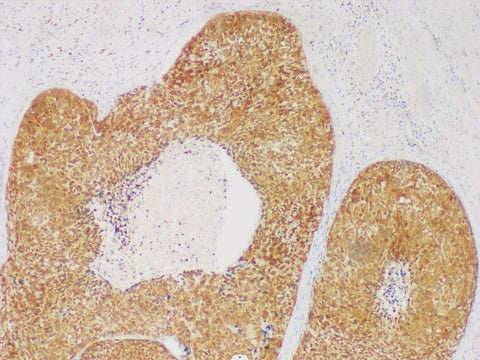

GST-P Monoclonal Antibody

Applications IHC-P

Tissue Specificity Esophageal Squamous Cell Carcinoma

Glutathione transferase-π (GST-π) is a multifunctional drug metabolizing enzyme, which is present in the cytoplasm and mitochondria of human cells. It is mainly distributed in the urinary, digestive and respiratory epithelium. At present, GST-π is mainly used in the study of cell resistance, which is related to cisplatin resistance.